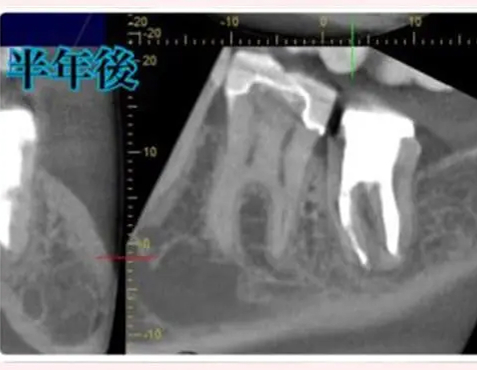

根尖病変によりCT上で黒く写っていた部分が白っぽくなっているのがわかりますか?

溶けていた部分の歯槽骨が回復しているということです!

また、上顎洞の肥厚は収まり、頬側の歯槽骨もくっきり映っています。予想以上に歯槽骨が回復しているので、今後外科的処置をしなくても良いのではないかと判断しました。大きなダメージがあった歯なので補綴物を入れた後も欠かさずに経過観察を行い、少しでも長くご自身の歯で生活して頂きたいと思います。